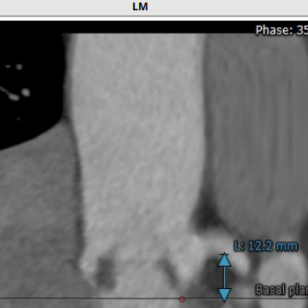

术前CT结果显示,患者主动脉瓣瓣环周长:67.4 mm,平均瓣环直径:21.5mm。左流出道平均直径20.9mm,瓦氏窦最小径31.7mm,窦管结合交界处(STJ)28.4mm,风湿性心脏病,三叶瓣,轻度钙化,瓣叶明显增厚,钙化,左冠开口高度12.2mm,右冠开口高度16.1mm,结合瓦氏窦内径,瓣叶长度及度钙化分布等综合因素考虑,冠脉风险较低,双侧入路血管直径尚可,无明显钙化,最小直径为5.5mm。

主动脉根部评估

冠脉阻挡风险评估及钙化程度分析